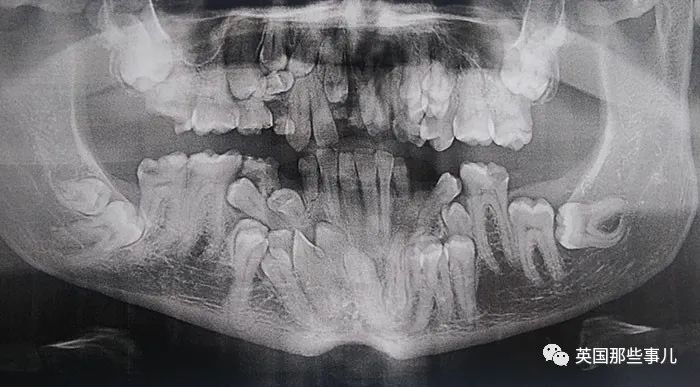

我被診斷出患有一種叫“顱骨鎖骨發育不全綜合症”的罕見病,

今天頭一次做X光,發現我的牙齒比別人多了好多.....

我已經做了10多年牙醫,但6-12歲孩子的口腔X光,還是那麽(me) 讓我著迷.....